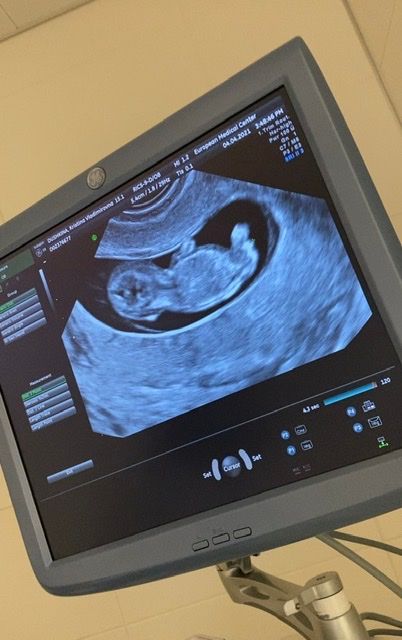

Добрый день. Сегодня была на УЗИ, срок 10 недель и 4 дня. Врач не сказала пол, говорит боюсь ошибиться. Кто разбирается в половых бугорках? Сдала НИПТ через 2 недели узнаю пол))

Я бы подумала,что мальчик)У девочек совсем лежачий бугорок,а у вашего чуть приподнят.

Вроде на девочку похожа) у меня в дневнике есть фото первого узи с половым бугорком,девочка у нас в животике)

Ирина, посмотрела ваш дневник) У вас она лежит более удачно и бугорок строго параллельно) А у меня вроде и параллельно, но с другой стороны и вверх тоже смотрит. Либо просто неровно лежит)) В общем, жду с нетерпением, НИПТ))

Мне кажется девочка. Я УЗИ делала в 12 недель, половой бугорок так же расположен, как у вас. В 16 недель сказали будет девочка. Вот теперь ждем второй скрининг, чтобы подтвердили)))